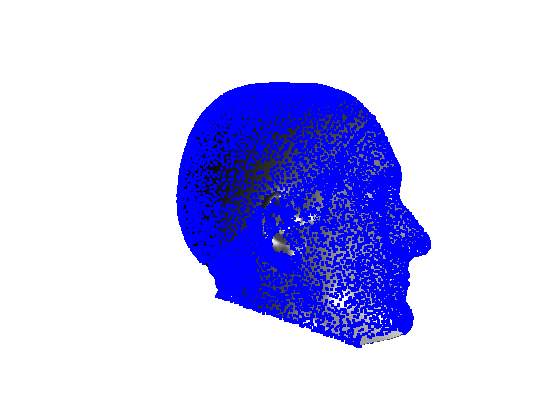

Following this, OSNR ICP iterates over a set of decreasing mesh stiffnesses (typically 10), until the registration between the template and the scan is below some error or a maximum number of iterations is reached. Figure 28 shows a selection of template warp results. The template appears to be accurately warped onto the scan, at least in the normal direction of the surfaces, it is not possible to see error tangential to the surface. Furthermore, we have noted errors on some scans on the ears. To improve these we need a method of automatically landmarking the ears, which is an area for further work.

|

|

|

|

|

|

|

|

The first two modes of head variation are shown in figures 29 and 30. These include the cranial height / facial angle mode and the (almost) pure size mode, as seen in the sagittal profile model.